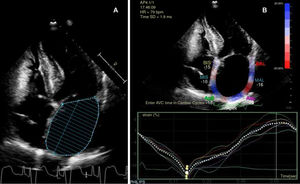

A la espera de los resultados, se continuó con el estudio y se la pasó a planta de hospitalización tras telemetría cardiaca de 24 h en ritmo sinusal y sin episodios de arritmias. La ecografía doppler de troncos supraaórticos mostraba placas de ateroma en ambos territorios carotídeos sin compromiso hemodinámico, mientras que en la valoración transcraneal no se apreciaron estenosis. Se realizó, una ecocardiografía transtorácica (ETT) con los resultados indicados en la tabla 1, ajustados de acuerdo con el área de superficie corporal (1,657 m2). El diámetro y área auricular son compatibles con AI ligeramente dilatada, mientras que los datos de volumen y actividad funcional, como la fracción de eyección de AI (FEAI) y el strain de AI (SAI), indican una afectación más grave de la cámara (fig. 1). Recibidos posteriormente los datos de registro del marcapasos, estos mostraron un episodio paroxístico de FA de 17 h de duración 3 meses antes y otro 4 días después del evento, con ritmo sinusal al momento de la clínica neurológica.

Si analizamos los resultados mostrados en la tabla 1 con las consideraciones aportadas sobre los distintos parámetros ecocardiográficos, un estudio ETT habitual en nuestro centro (valoración de AI a través de diámetro anteroposterior y área) solo hubiera mostrado una cámara ligeramente dilatada, cuando en realidad nos encontramos ante una grave dilatación auricular de acuerdo con los datos volumétricos (tabla 2). Este resultado, que de otra manera hubiéramos pasado por alto, permite asociarlo no solo con una mayor incidencia de FA sino también con recurrencia de ictus14. Por su parte, el descenso de la FEAI por debajo del 50% y un SAI en fase reservorio inferior al 25,8% también enfocarían hacia una posible FA paroxística subyacente10,11.